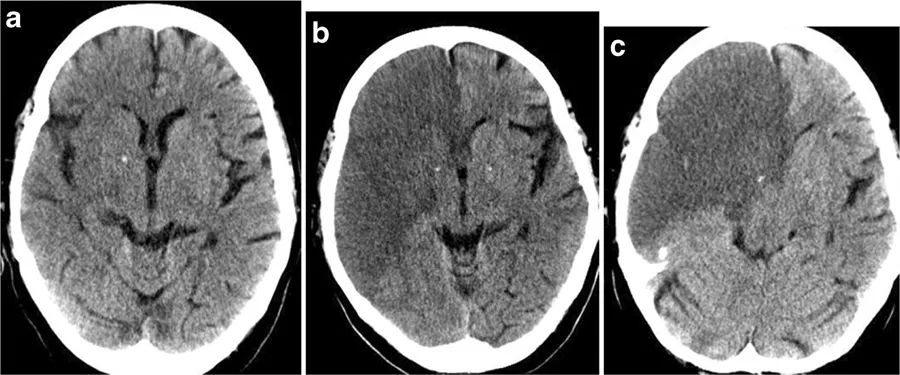

图1 62岁男性,突发左侧偏瘫87分钟后完成了CT扫描,但CT上并未检测出患者的细胞毒性脑水肿,小脑半球上两个微小的病变并不能对症状做出解释(a~d)。症状发作后3小时10分钟,患者完成了MRI扫描,DWI显示患者大脑和小脑半球显现出多发栓塞情势的小病灶,大脑半球右侧为著,这解释了患者的卒中症状(f~h)。经进一步检查,本例患者有主动脉夹层。